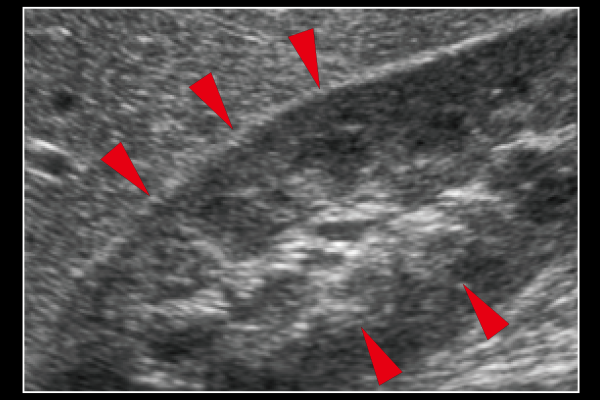

周囲組織の質感や表現を保ちながら、血管壁などの組織構造を明瞭に描出します。進化したエッジ強調処理技術によって、構造物を効果的に抽出することが可能です。

Carving Imaging OFF